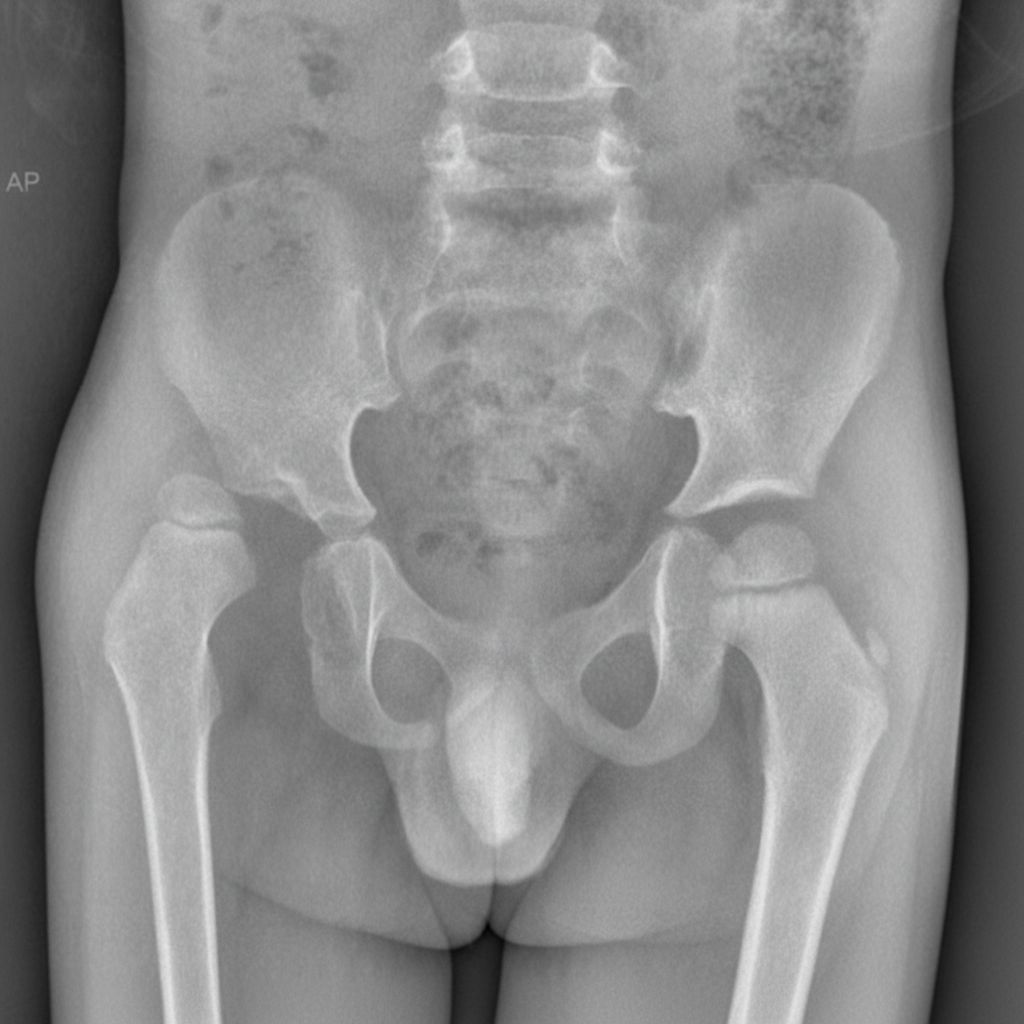

A 7-year-old boy is brought to the physician by his mother because of a limp for the last 3 weeks. He has also had right hip pain during this period. The pain is aggravated when he runs. He had a runny nose and fever around a month ago that resolved with over-the-counter medications. He has no history of serious illness. His development is adequate for his age. His immunizations are up-to-date. He appears healthy. He is at the 60th percentile for height and at 65th percentile for weight. Vital signs are within normal limits. Examination shows an antalgic gait. The right groin is tender to palpation. Internal rotation and abduction of the right hip is limited by pain. The remainder of the examination shows no abnormalities. His hemoglobin concentration is 11.6 g/dL, leukocyte count is 8,900/mm3, and platelet count is 130,000/mm3. An x-ray of the pelvis is shown. Which of the following is the most likely underlying mechanism?